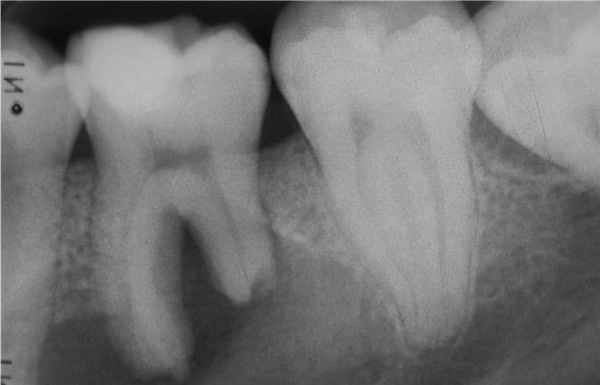

Диаметр наружной периодонтальной кисты очень мал. На снимке легко увидеть, что он образуется на боковой поверхности корня зуба. При обнаружении бокового периодонтита (опухоли периодонта) его можно лечить без нарушения зубного ряда.

Радикулярные (одонтогенные воспалительные) кисты образуются на корнях зубов вследствие патологических процессов, распространяющихся за верхушкой корня. По расположению радикулярные кисты могут быть апикальными (корневыми), латеральными (боковыми), апико-латеральными и межкорневыми.